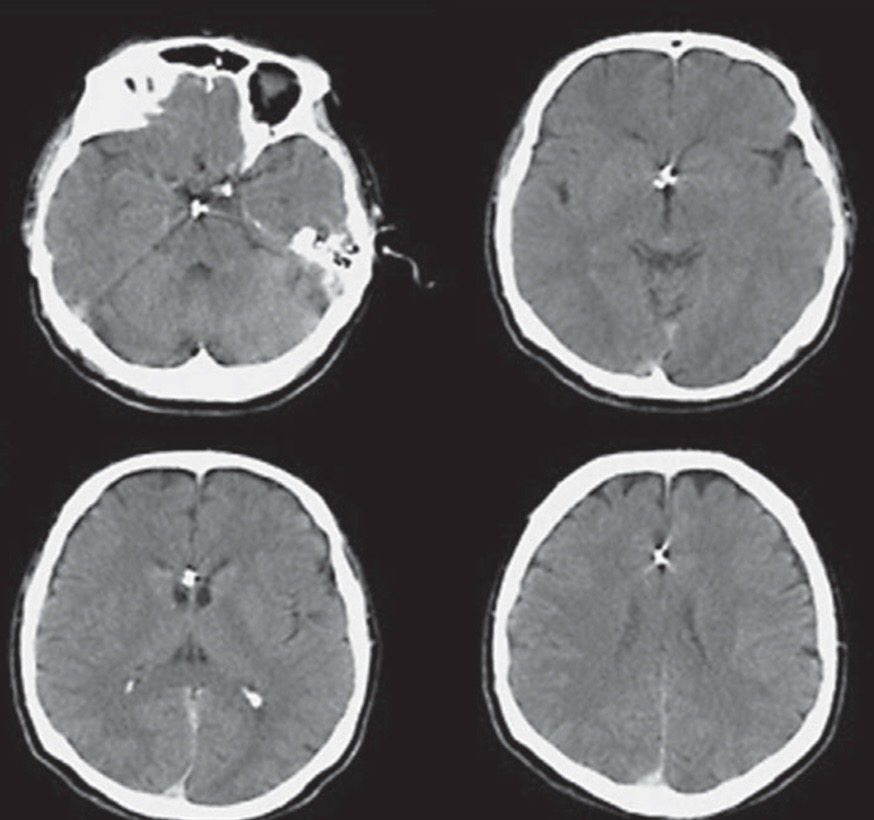

НемедицинаFigure 2. Аксиальные снимки компьютерной томографии, показывающие иглу в головном мозге.